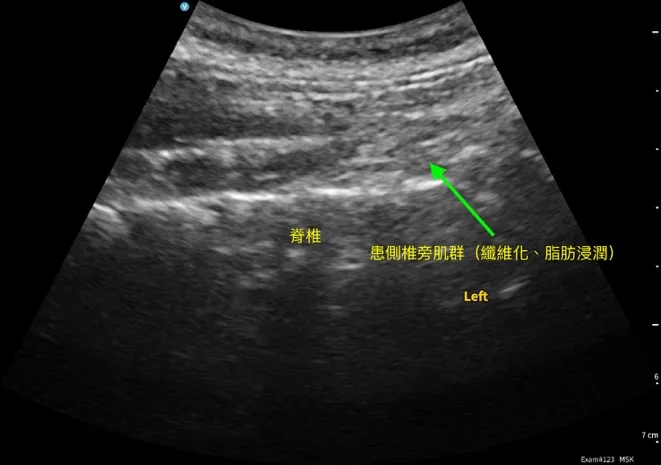

我使用超音波由頸部前外側向後檢查椎間盤健康狀態,看到 C5/6/7 段椎間盤變扁,並伴隨小鈣化訊號。 再往頸部側邊掃描,在神經根出口附近,探頭輕壓就能誘發她熟悉的痠痛與痠麻。 同時在頸部後側椎旁肌群,與健側比較,下段也呈現明顯纖維化與脂肪浸潤樣態。

這些發現讓我判斷:除了椎間盤本身,神經根出口周邊的高張力與沾黏軟組織很可能是讓症狀被持續放大的關鍵。

- 超音波線索:C5/6/7 段退變相關訊號;神經根出口附近輕壓可誘發熟悉痠麻;下段椎旁肌結構改變(纖維化/脂肪浸潤樣態)。